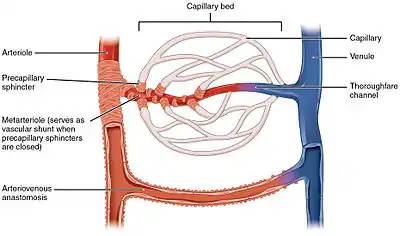

Arteries branch into small passages called arterioles and then into the capillaries.[19] The capillaries merge to bring blood into the venous system.[20]

Capillaries merge into venules, which merge into veins.[21] The venous system feeds into the two major veins: the superior vena cava – which mainly drains tissues above the heart – and the inferior vena cava – which mainly drains tissues below the heart. These two large veins empty into the right atrium of the heart.[22]